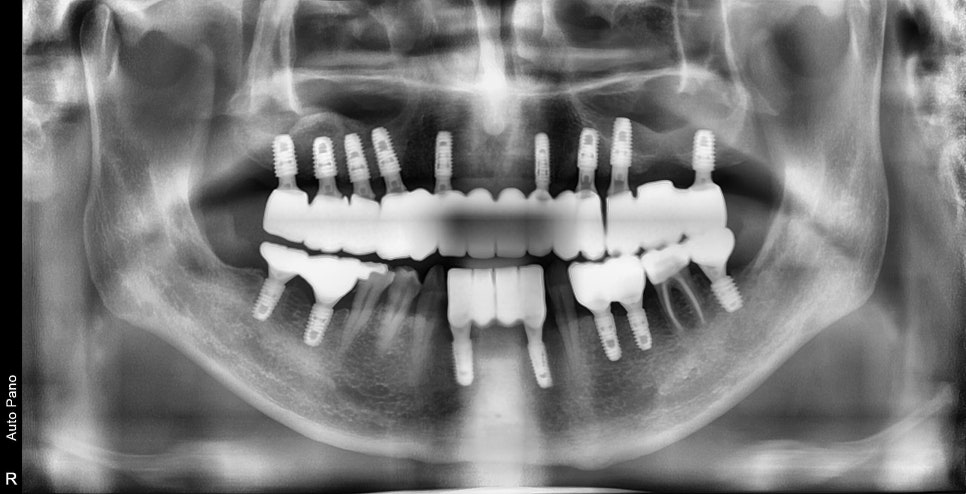

이비인후과 수술 후 경과

이비인후과에서 비염 수술을 하신 후

3달 정도가 지난 사진입니다.

과거에 상악동을 채우고 있던 희뿌옇던 염증이 사라졌지만

만성 염증에 의해 점막이 부어있습니다만

이 정도는 상악동거상술을 하기에는 방해요소는 아닙니다.

상기 환자는 남아있는 잔존골의 양이 너무 적기 때문에

측면에서 접근하는 측방접근법을 이용하여

치조골 이식술과 동시에 임플란트 수술을 했습니다.

교합 안정화 후 최종 보철물 제작

불안정했던 턱관절과 교합을 안정화 시킨 후

더 이상 교합의 변화가 일어나지 않을 때

임시보철물 -> 최종보철물로 제작을 진행했습니다.

전체 치료가 완료되었지만

주기적으로 보철물의 체크와 상악동내의 상악동염이 재발하는지를 체크해야 할 것입니다.

치료 전 / 후 사진을 보게 되면

아래턱이 돌출된 부정교합 케이스로 보철 제작 시

윗니가 아랫니를 덮는 교합으로 제작을 해줘야 합니다.

턱의 돌출 정도와 내려앉은 치조골의 양에 따라서

보철의 디자인으로 충분히 커버를 해줄 수 있습니다.